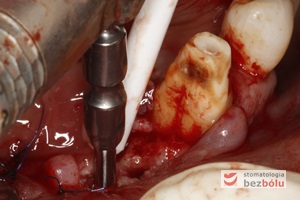

Piesosurgery - przyjazne dla pacjenta i chirurga - wstępne opracowanie łoża implantów za pomocą piesosurgery (piezochirurgia)

Piesosurgery – przyjazne dla pacjenta i chirurga – wstępne opracowanie łoża implantów za pomocą piesosurgery (piezochirurgia)

Opracowanie łoży implantów - poszerzanie łoży implantów oraz zagęszczanie kości przy użyciu techniki osteotomowej

Opracowanie łoży implantów – poszerzanie łoży implantów oraz zagęszczanie kości przy użyciu techniki osteotomowej